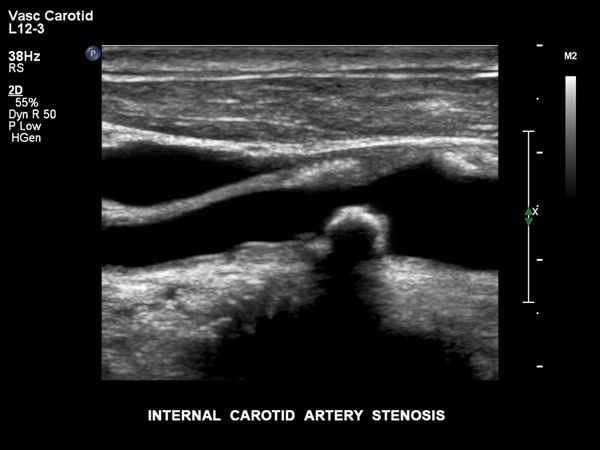

vaskular.pdf

kardio-vaskular.pdf